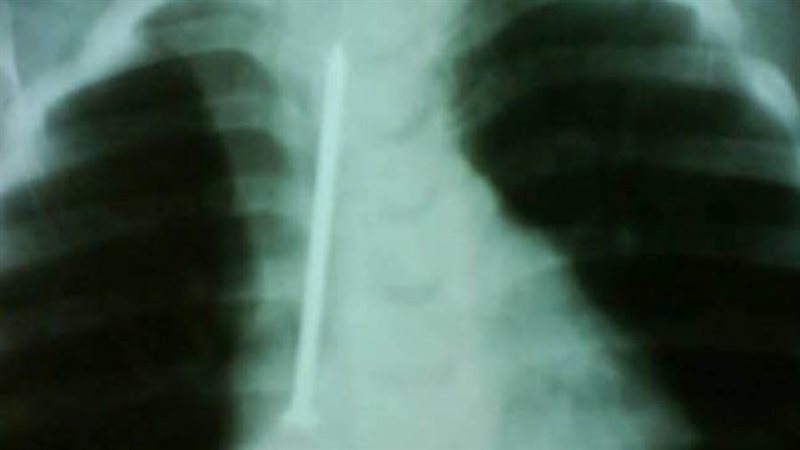

وأضاف قائلًا: "كانت الطفلة في حالة طبيعية تمامًا، تتنفس بشكل جيد ولا تعاني من أي صعوبة في البلع، لكن أمام إصرار الأم على أنها بحثت جيدًا في المنزل، قررت إجراء أشعة على صدر الطفلة، لتظهر المفاجأة الصادمة مسمار طويل يمتد بطول القفص الصدري تقريبًا".